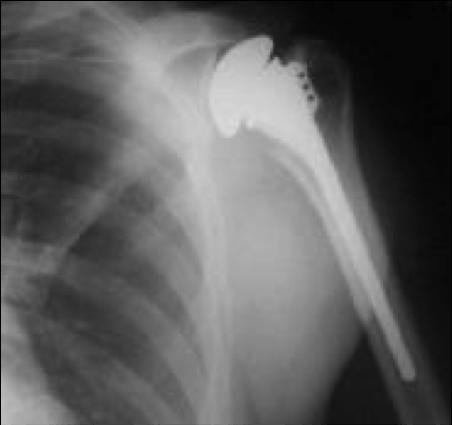

위의 사진과 같이 기존의 인공관절은 humerus 의 골두를 제거하고 glenoid 모습과 비슷하게 작동하는 원리로 인공관절이 되었으나 최근에는 humerus head 의 medialization 효과와 deltoid muscle lever arm의 증가로 더 효과가 있는 reverse shoulder arthroplasty 가 많이 시행되고 있습니다. 1990년대부터 수술을 시작했으니 30년 정도 지난 수술법입니다.

쉽게 생각하면 Convex 와 Concave가 반대로 된 구조라고 생각하면 됩니다. 회전의 중심(Center Of Motion)이 좀더 아래와 안쪽에 위치한 생역학적 장점을 갖고 있습니다.